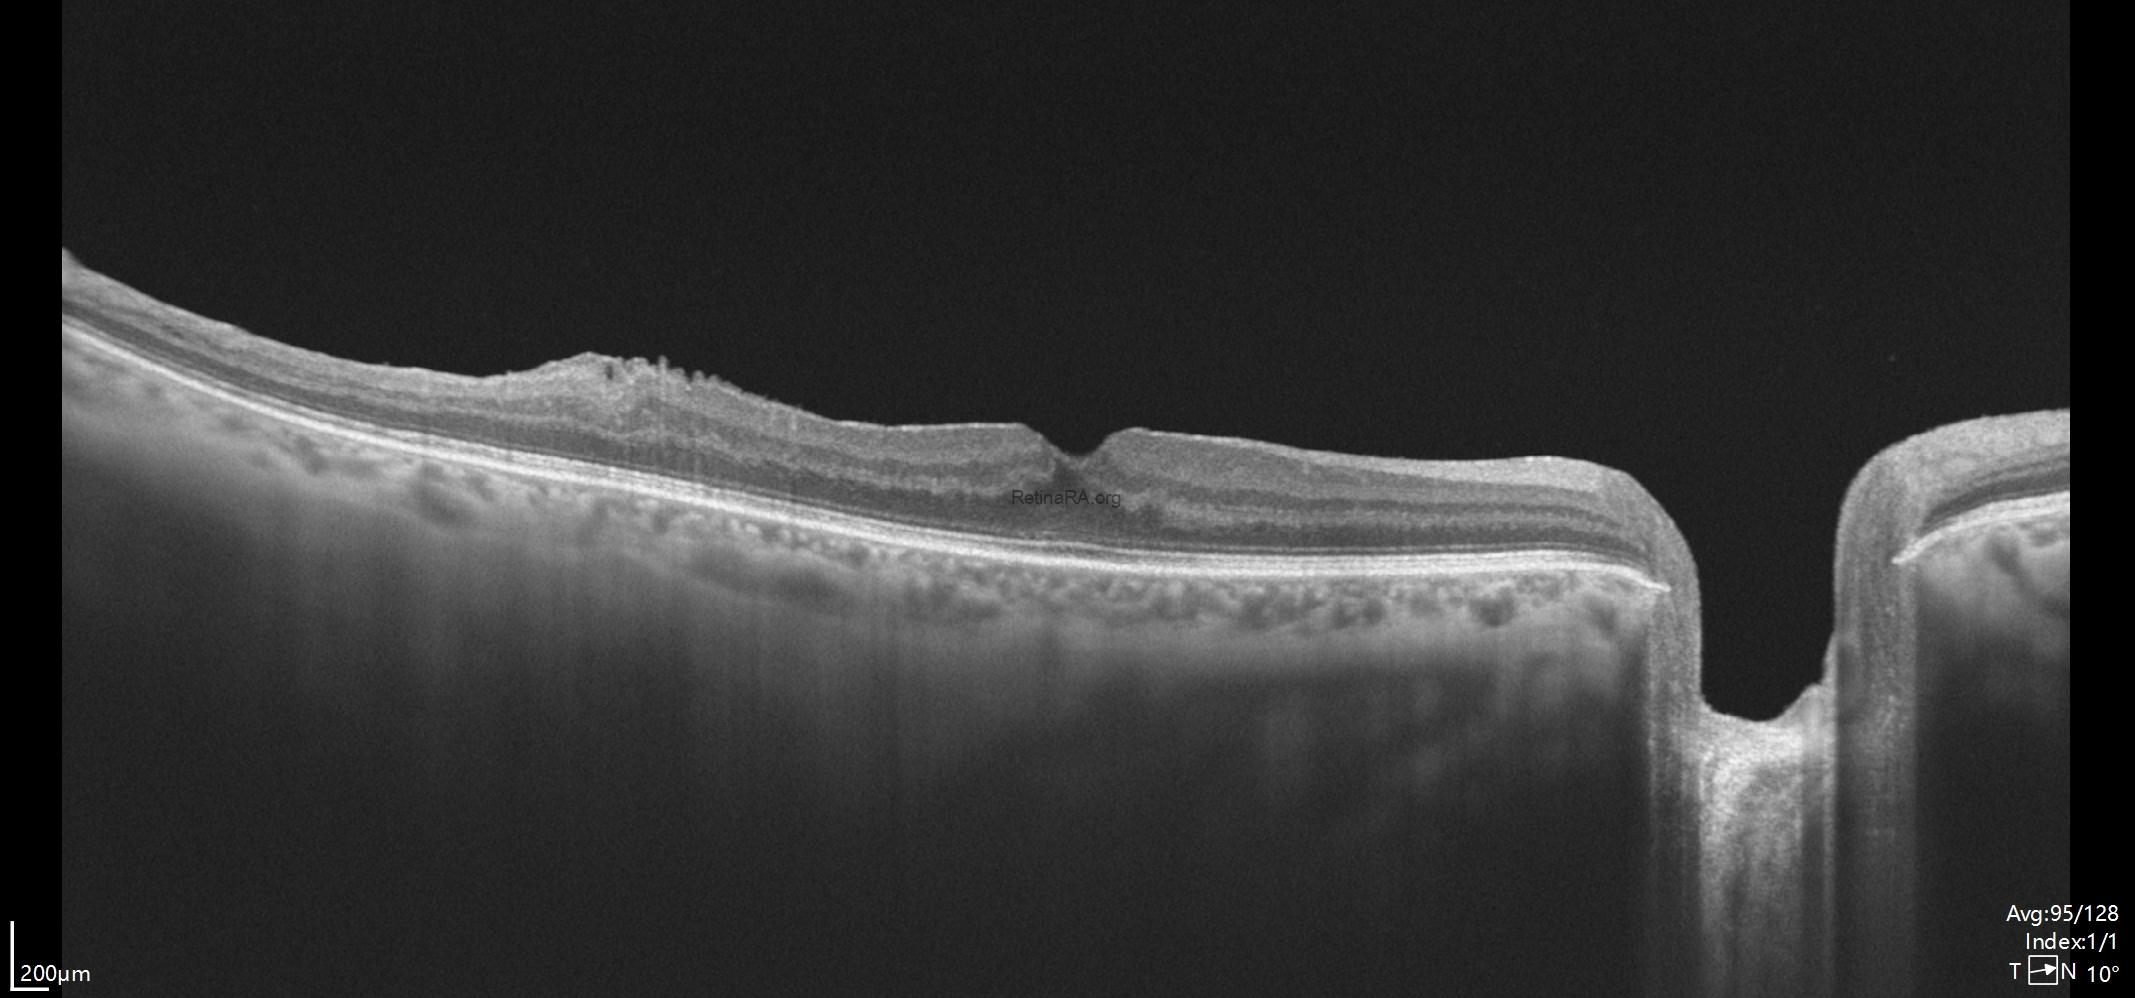

Five month after surgery, restoration of the foveal depression was observed. Even in the temporal macular region where a portion of the membrane was intentionally left, the retinal architecture showed a significant improvement compared to the preoperative state. Visual acuity improved to 20/20.